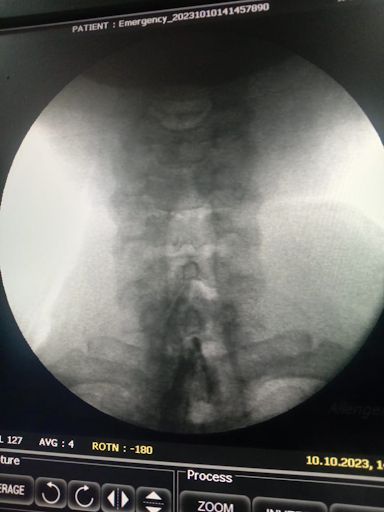

- X-ray cervical spine – shows osteophytes and disc space narrowing.

- MRI – reveals disc degeneration, spinal canal narrowing.